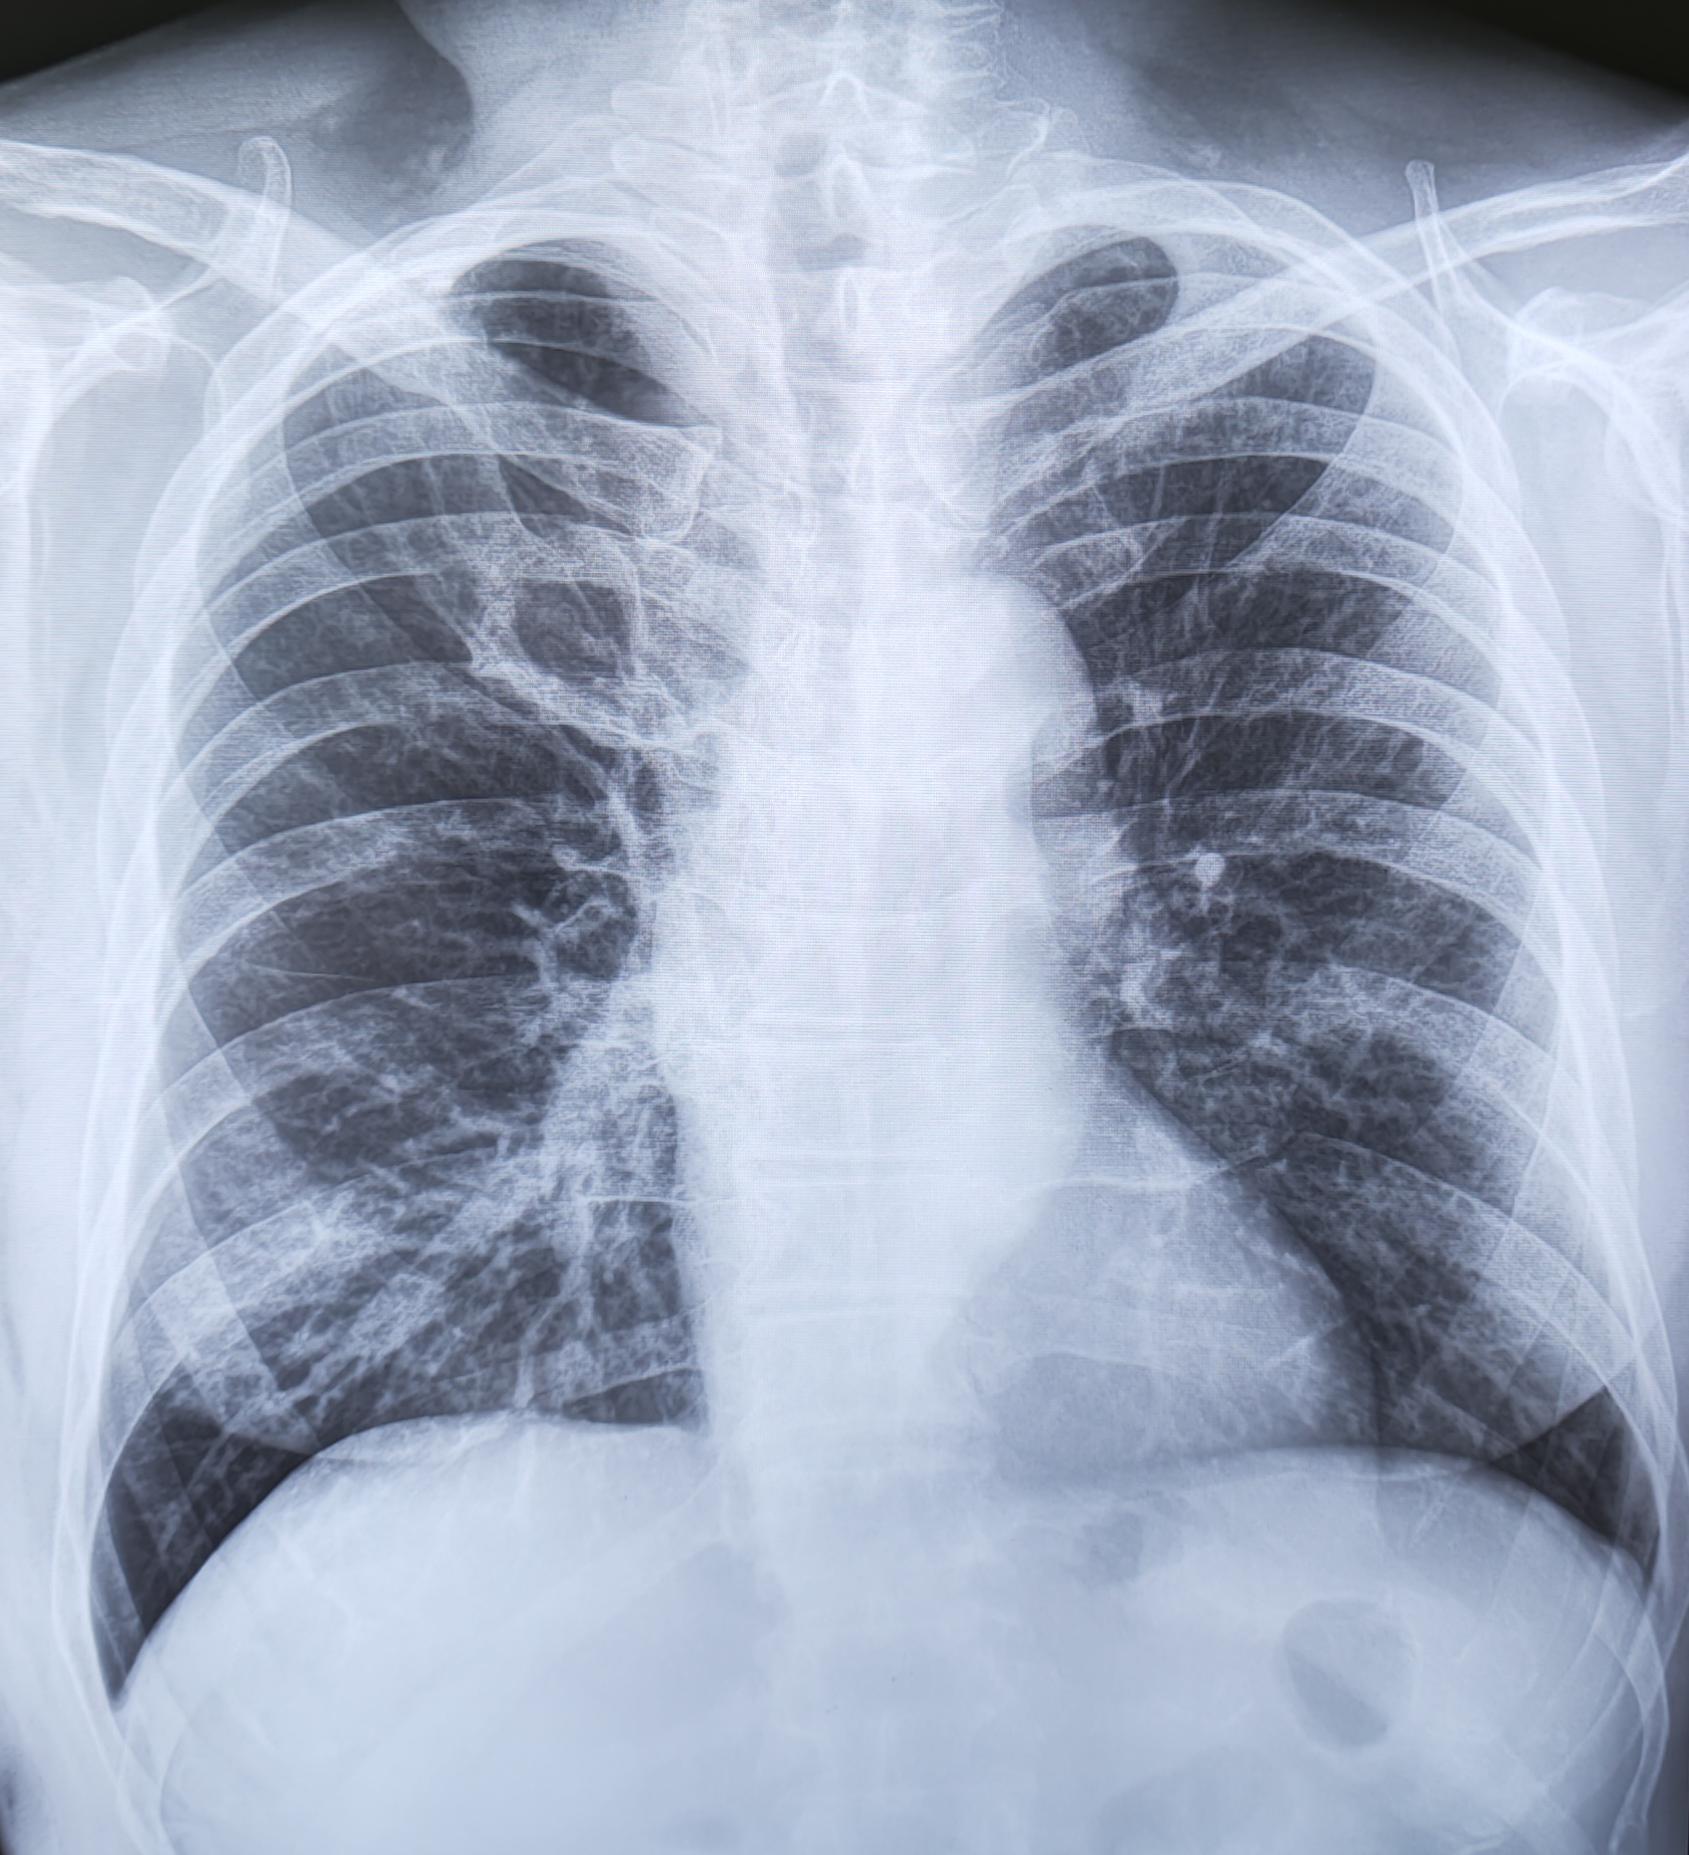

Ребро Люшка

Ребро Люшка - врожденная аномалия развития ребра в виде удвоения его переднего отдела